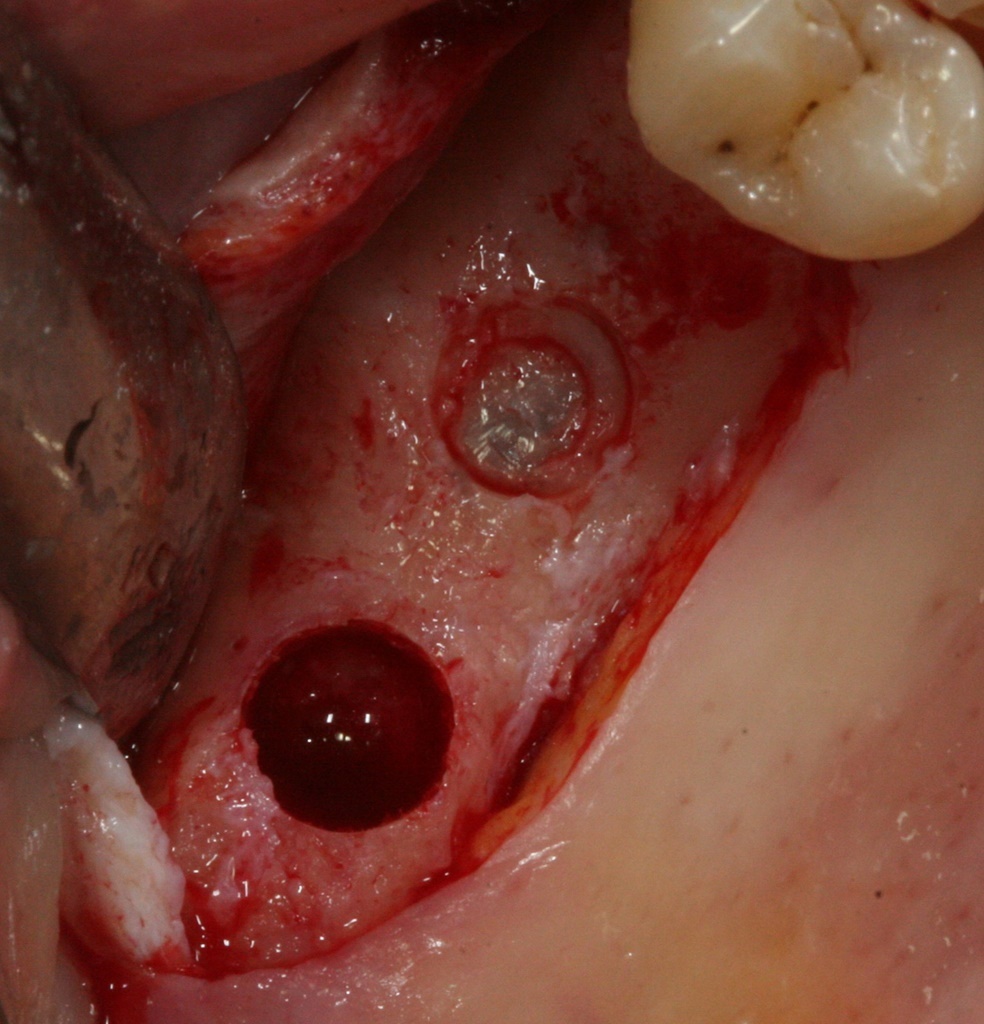

Eine speziell sichere Technik des Internen Sinusliftes.

Alles was Sie über die Operationstechnik wissen müssen (Lateraler und interner Sinuslift im Vergleich. Ist der Sinuslift wirklich so schwierig?)

Theoretische und wissenschaftliche Hintergründe. Anatomie, Instrumente, Bildgebende Verfahren, Schnittführung, Weichgewebsmanagement, Primärstabilität, Knochenqualität, Implantat Belastung. OP-Schritte step by step in live OP HD Videos, Freilegung.

Praktisch orientierter Lehrstoff, der durch Operationsvideos in HD Qualität und Fotos step by step demonstriert wird.